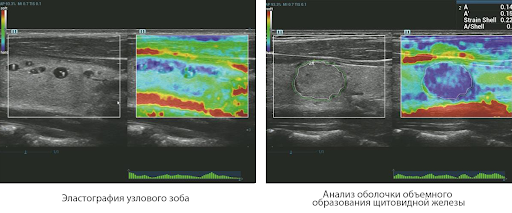

Метод эластографии Natural Touch

Natural Touch обеспечить непревзойденную чувствительность и отличную воспроизводимость результатов вне зависимости от навыков оператора, повышает клиническую значимость метода и расширяет возможности его применения. Уникальный анализ зоны ободка — исключительно полезный инструмент для оценки доброкачественных и злокачественных образований— предоставляет данные о коэффициенте деформации между окружающей тканью и пораженным участком, что позволяет оценить степень инфильтрации раковых клеток в окружающие опухоль ткани.